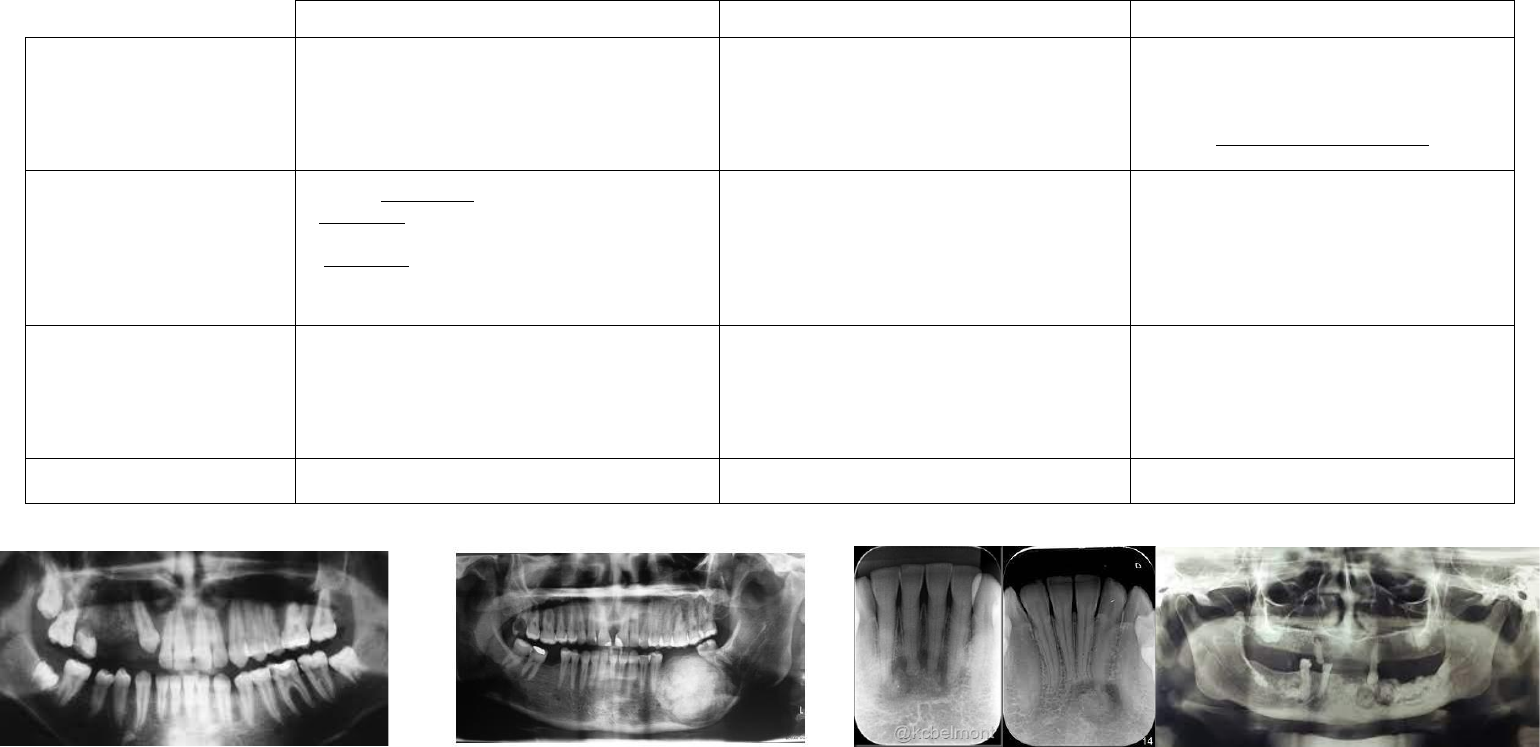

Apresentação radiográfica

Radiolúcida (início), mista ou radiopaca (vidro

despolido – lesão parece se misturar com o osso

adjacente); difusa; tamanhos variáveis; provoca

deslocamento dos dentes; reabsorção radicular, perda

da lâmina dura; abaulamento das corticais; fratura

patológica é rara.

Lesões iniciais radiolúcidas, com o passar do tempo,

tornam-se mistas (focos radiopacos). Expansivas e de

bordas bem demarcadas, frequentemente

corticalizadas.

Lembra o aspecto de um odontoma, mas o fibroma

tem proporções maiores.

Imagem radiolúcida, mista ou radiopaca de

limites bem definidos; requentemente um halo

radiolúcido pode estar presente; pode haver

descontinuidade da lâmina dura; lesões menores

não estão associadas a expansão de corticais.